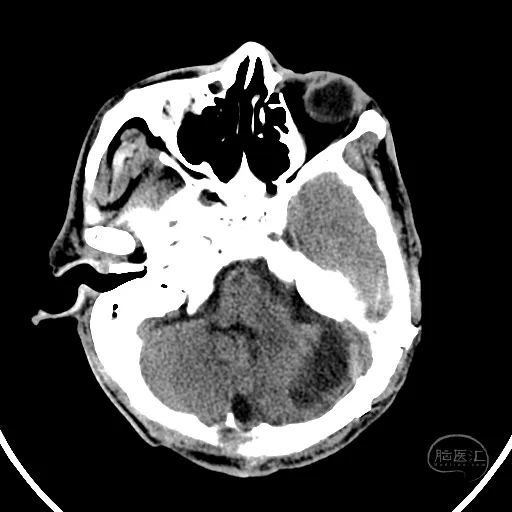

2小时后复查颅脑CT显示第四脑室受压消失。

小脑挫伤灶水肿较前加重,脑干及小脑半球低密度改变。

硬膜外血肿无明显变化。

右额叶脑挫裂伤并脑内血肿形成,中线结构明显移位。

左侧脑室有扩张表现。

此时患者双侧瞳孔散大,GCS评分4分,气管插管,自主呼吸。家属同意手术治疗。

幕上脑疝,幕下压力也高,第四脑室闭塞,导水管显示不清,脑室有扩张表现。